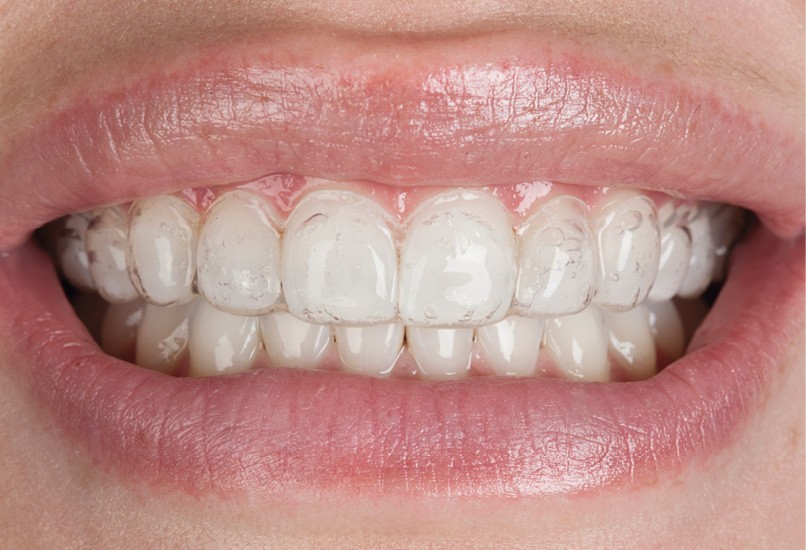

Depuis quelques années, les techniques évoluent. À côté de ces protocoles classiques, une nouvelle approche s’impose : l’éclaircissement sans empreinte, reposant sur l’utilisation de gouttières préchargées prêtes à l’emploi. Parmi ces solutions, Opalescence Go® occupe une place de référence (fig. 3).